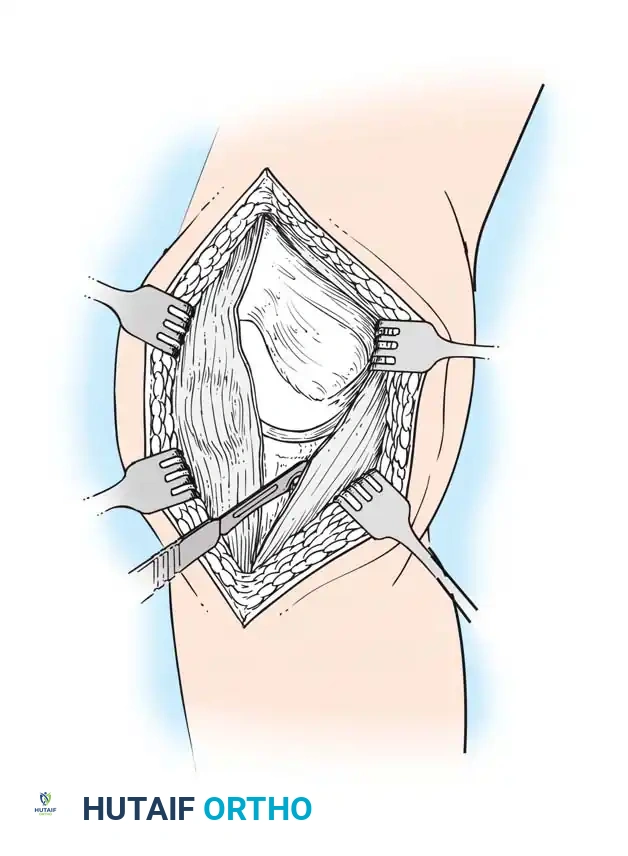

The Subvastus ("Southern") Approach

In an effort to reduce patellofemoral complications and expedite the return of quadriceps function, alternative methods of exposure have been developed. The subvastus approach, advocated by Hofmann, Plaster, and Murdock, avoids violating the extensor mechanism.

- The same anterior midline skin incision is used.

- The proximal retinacular incision is performed by incising the superficial fascia overlying the vastus medialis.

- Bluntly mobilize the distal medial border of the vastus medialis posteriorly to the medial intermuscular septum.

- Lift the origin of the vastus medialis off the medial intermuscular septum to approximately 10 cm proximal to the adductor tubercle, staying distal to the aperture for the femoral vessels.

- Incise the synovium and dislocate the entire extensor mechanism laterally.

Advocates of the subvastus approach note that leaving the extensor mechanism intact results in a more rapid return of quadriceps strength, preserves the vascularity to the patella (specifically the supreme genicular artery), decreases postoperative pain, and reduces the need for lateral retinacular release. However, exposure can be severely limited in obese patients, highly muscular individuals, or those with previous knee surgeries.

The Midvastus Approach

Engh and Parks described the midvastus approach, which serves as a compromise between the extensile nature of the medial parapatellar and the quadriceps-sparing nature of the subvastus approach.

- The vastus medialis muscle is split in line with its fibers rather than subluxated laterally in its entirety.

- The split begins at the superomedial border of the patella and extends proximally and medially toward the intermuscular septum.

- A safe zone of 4.5 cm of the vastus medialis can be sharply split from the patellar margin; further blunt dissection can be performed if necessary.

This approach preserves the supreme genicular artery and the quadriceps tendon. Relative contraindications include severe obesity, previous upper tibial osteotomy, and preoperative flexion of less than 80 degrees. Careful hemostasis is mandatory, as postoperative hematomas are more frequently described with muscle-splitting approaches.